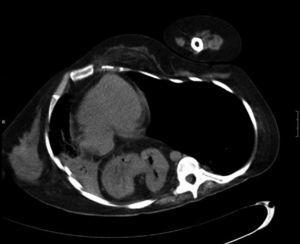

Mujer de 33 años, diagnosticada de tetraparesia secundaria a mielitis transversa a los 2 años de edad. Como secuelas desarrolló cifoscoliosis grave con alteración ventilatoria restrictiva. Sus cuidadores le aplicaban de forma continuada la técnica de tos asistida con compresión abdominal para facilitar la eliminación de secreciones bronquiales. Acudió al Servicio de Urgencias por proceso febril de menos de 24 h, disnea y dificultad para eliminar secreciones respiratorias. En la exploración física se apreciaban murmullo vesicular disminuido en el hemitórax derecho y estertores de secreciones bronquiales en el izquierdo. Los datos de la gasometría arterial fueron los siguientes: fracción inspiratoria de oxígeno de 0,28, pH de 7,39, presión arterial de anhídrido carbónico de 43,7 mmHg, presión arterial de oxígeno de 68,3 mmHg, HCO3 de 24,7 mmol/l y saturación arterial de oxígeno del 93,4%. La radiografía de tórax evidenció cifoscoliosis grave y opacidad completa del pulmón derecho, que no estaba presente en la tomografía axial computarizada (TAC) realizada 6 meses atrás. Con el diagnóstico de atelectasia derecha debida a posible ocupación por secreciones bronquiales y cuadro febril secundario a infección respiratoria, se inició tratamiento antibiótico (cefotaxima). En la sala de hospitalización de neumología se complementó el tratamiento con fisioterapia respiratoria y tos asistida mecánica (Cough-Assist®). A partir del quinto día la paciente presentó mejoría clínica, pero persistió la hipofonesis en el hemitórax derecho. Se solicitó TAC torácica, que mostró colapso de casi todo el pulmón derecho, secundario a compresión por hernia de hiato que contenía prácticamente todo el estómago y grasa abdominal (fig. 1). Al comparar dicha TAC con la realizada 6 meses atrás se observó una progresión considerable de la hernia, que antes era de pequeño tamaño. Se indicó a los cuidadores que practicaran maniobras de hiperinsuflación con resucitador manual (Ambú®) y compresión torácica como asistencia adicional a la tos. A las 3 semanas del alta el control radiológico mostró práctica resolución de la opacidad en el hemitórax derecho.

Fig. 1. Tomografía axial computarizada que muestra contenido abdominal (grasa y parte del estómago) en el hemitórax derecho.